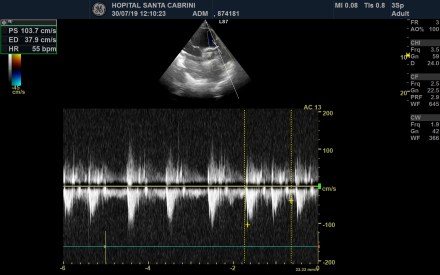

Venous #POCUS Case Discussion. #VEXUS #FOAMed #FOAMcc